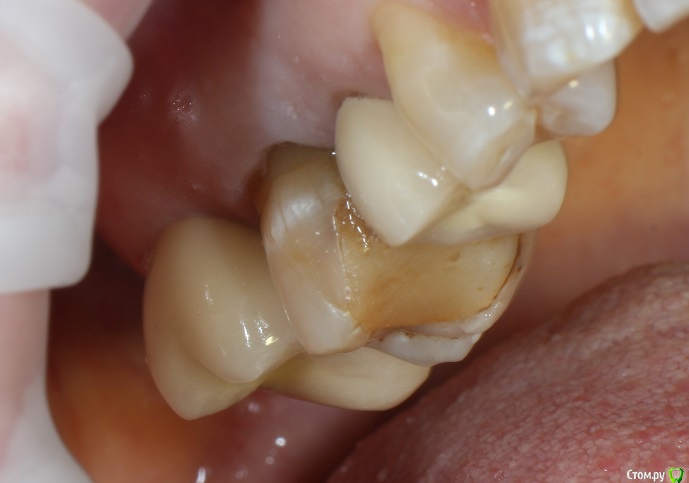

06.06.2019 в 12:59, kuziy12 сказал:

В начале своей карьеры...давным давно...где-то год назад удалял верхнюю восьмерку. Тогда я не знал, что при наличии пломб-залипух на соседних зубах, нужно предупреждать, что они могут вылететь. Что и произошло с 1.7 Пациент оказался адекватным, все понял, сказал через неделю придет, поставим пломбу и happy end. Прошел год - пришел пациент. На мое предложение удалять, так как от зуба немного осталось, а неделя неравна году, была сказана фраза: "на соседнем зубе тоже пломба-залипуха, так я вообще без зубов останусь". Ну надо воевать, подумал я. Изначального фото ситуации нет, но там пришлось убирать достаточное количество десны. (За фото прошу не пинать, бить только руками)

Стандартная обработка машинными, с кофером, ГХ, блекджеком и...

Пломба(СО ШТИФТОМ), сильно полировкой заморачиться не стал, так как в это же посещение обработка под МК

Собственно господин преп

Стандартный оттискной(деревня же)

Фото на модели:

Фото зафиксированной коронки

Спасли комбайнеру зуб! Тяжело так, но уверенно нарабатывате базу пациентов.